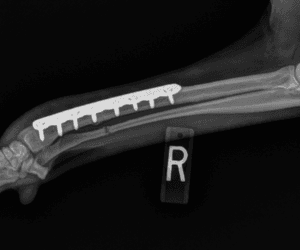

Fracture Repair

Unfortunately, just like people, fractures (broken bones) are common in both dogs and cats. There are many different types of fractures and pre-operative assessment of radiographs is essential to plan the specific surgical fixation required. Although fractures can be traumatic for both pets and their owners, with proper stabilization and postoperative care, fractures will heal and the pet can return to normal.

$2500-3500

Tibia – $3000

Femur – $3250

Radius/Ulna – $2750

Humerus – $3500

Femur Physeal Fracture – $2750

Tibial Tuberosity Physeal Fracture – $2500

Humeral Physeal Fracture – $3500